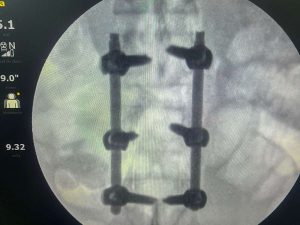

O paciente, Luciano Francisco, de 41 anos, foi atropelado por um carro na madrugada de sábado, enquanto se dirigia ao trabalho de bicicleta. Com o impacto, ele sofreu uma fratura na coluna lombar e perdeu os movimentos dos membros inferiores. Diante da gravidade do quadro, a equipe médica interviu com agilidade e organizou a realização da cirurgia já no dia seguinte, ontem domingo (8).

O procedimento, que durou 1h45, foi conduzido pelos ortopedistas especialistas em coluna, doutor Marlon Mendonça e Paulo Splenger, com apoio da equipe de trauma da unidade. Segundo o médico, a cirurgia transcorreu com sucesso e sem intercorrências. “O paciente chegou lúcido à UTI e já estava conversando após o procedimento. A expectativa agora é acompanhar a evolução neurológica, que depende do tempo e da resposta do organismo”, explicou doutor Marlon.

A intervenção teve como objetivo a descompressão da medula e a estabilização da coluna, medidas urgentes para minimizar os danos causados pelo trauma. “É um marco. Iniciamos um novo capítulo para o hospital, com a realização de cirurgias de alta complexidade que antes não eram possíveis. Isso representa mais qualidade, mais dignidade e menos sofrimento para os nossos pacientes”, afirmou doutor Paulo Splenger.